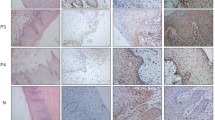

The cytoplasmic, perinuclear and nuclear pattern of Foxp3 immunoexpression on tumor infiltrating cells was seen in all OSCC cases and 9 control cases. Tumor cells were devoid of Foxp3 staining. CD4 and CD8 were clearly stained in the cell membrane of infiltrating cells of control and OSCC cases. The immunoexpression of PD-L1 in cancer cells was predominantly cytoplasmic although membranous expression was also noted. Membranous PD-L1 immunoexpression was predominantly detected on infiltrating cells. In our study PD-L1 was expressed on cancer cells and tumor-infiltrating lymphocytes as well as epithelial, vascular endothelial and infiltrating cells of control cases. The cytoplasmic immunoexpression of PD-L1 on cancer cells was noted in 37 of 41 cases of SCCPP group, in 25 of 37 cases of SCCBP group, and in 16 of 18 control cases.

The semiquantitative and quantitative data on the immunoexpression of PD-L1, Foxp3+, CD4+ and CD8+ cells appear in Table 1. The immunoexpression of PD-L1 and the mean number of Foxp3+ cells was significantly increased in OSCCPP group (Figs. 1 and 2), in comparison to OSCCBP (Figs. 3 and 4) and control groups (Figs. 5 and 6). We also found significantly higher immunoexpression of PD-L1 and number of Foxp3+ cells in OSCCBP compared to control group. The mean number of CD4+ cells was significantly increased in OSCCPP group (Fig. 7) in comparison to both OSCCBP (Fig. 8) and control groups (Fig. 9). CD8+ cells were significantly more frequent in OSCCBP group (Fig. 10) in comparison to OSCCPP (Fig. 11) and control group (Fig. 12).